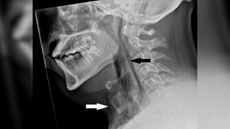

A man held in a sneeze — and it punctured his windpipeA man tore his windpipe, in part, due to hay fever.